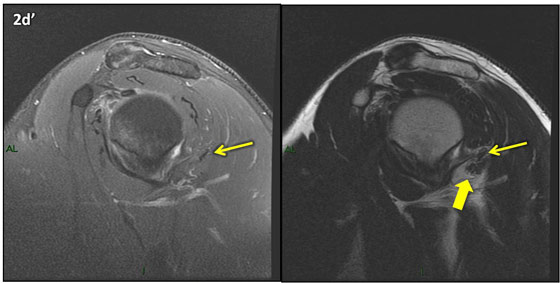

Figura 2 (a-j)': Imagens consecutivas de RM no plano sagital nas ponderaçõesT2 com supressão de gordura (DP SG) à esquerda e T2 à direita. Clique na seta para passar as imagens.

Figura 2a’ mostrando os tendões do subescapular (seta rosa), da cabeça longa do bíceps (seta verde), do supraespinhal (seta vermelha), do infraespinhal (seta laranja) e do redondo menor (seta amarela).

Figuras 2b a 2j’: Acompanhando o tendão do redondo menor (seta amarela fina) é possível notar lipossubstituição ao redor da junção miotendínea (setas amarelas grossas) e a atrofia principalmente da porção mais lateral (seta salmão). A porção mais medial (seta branca) tem volume preservado.

Repare que estas alterações também não são evidentes nas imagens com supressão de gordura no plano sagital.